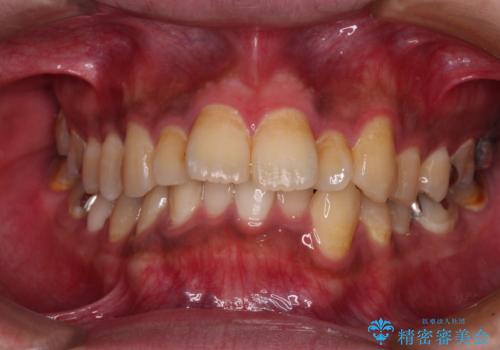

- 前歯のデコボコを治したいとのことで来院された患者様です。

上下顎ともに歯列全体の側方拡大とIPR(歯と歯の間を削る)によってデコボコが解消するように設計し、インビザラインにより治療を行うこととしました。

後方移動に際し、残っていた上顎の親知らずを抜歯することとしました。